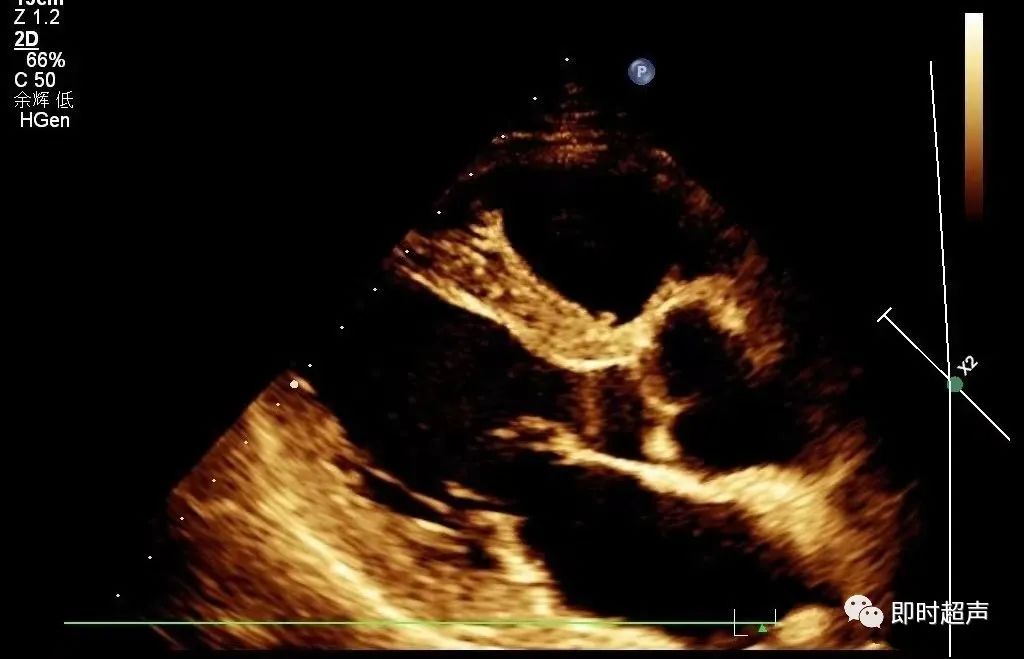

★主动脉的测量

测量切面:胸骨旁左室长轴切面;测量时相:舒张末期;测量:主动脉瓣环径、主动脉窦部内径、窦管交界处上方2cm处的近端升主动脉内径。